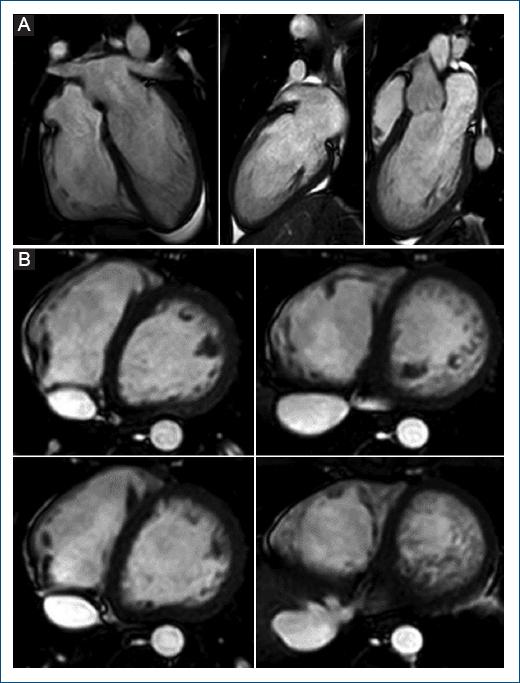

A 17-years-old white male patient with no personal history of interest and asymptomatic from the cardiovascular point of view, but with a family history of paternal grandfather with dilated cardiomyopathy and mild depressed left ventricle ejection fraction (LVEF) who died at 83 years of age of a noncardiological cause. In an electrocardiogram (ECG) performed during a sports examination (field hockey player), T-wave inversion (TWI) was identified in the inferior leads (Fig. 1). For further evaluation, an echocardiogram was performed, showing a pattern of hypertrabeculation in the inferior, lateral, and apical walls of the left ventricular, which was confirmed by cardiac magnetic resonance imaging (Fig. 2A and 2B), fulfilling the criteria for noncompaction, with no other notable findings. As a result of these findings, the 57-year-old boy’s father, who was asymptomatic cardio-vascular and had a non-pathological ECG, was also evaluated and showed noncompaction cardiomyopathy with normal LVEF.